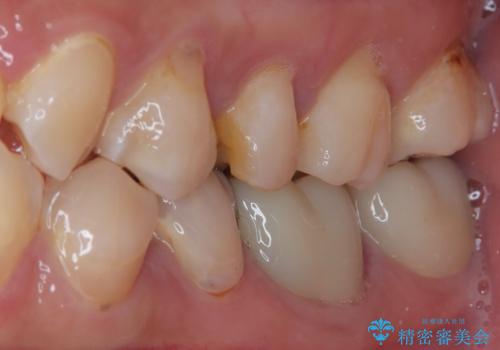

適合もよく、機能的に問題もなく、見た目も満足されていました。